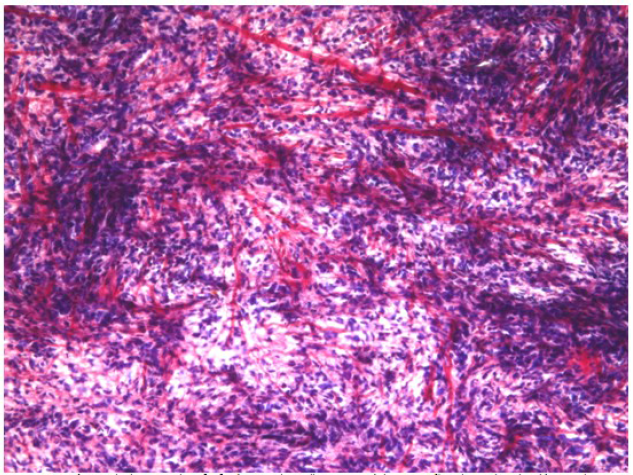

Se realizó también la coloración de hematoxilina fosfotúgstica de Mallory en la definición del posible origen muscular estriado de la lesión, el cual fue descartado al no identificarse fibras coloreadas de azul. (Figura 5).

Se definió finalmente el origen muscular liso de la tumoración concluyéndose el caso como un leiomiosarcoma cardiaco.